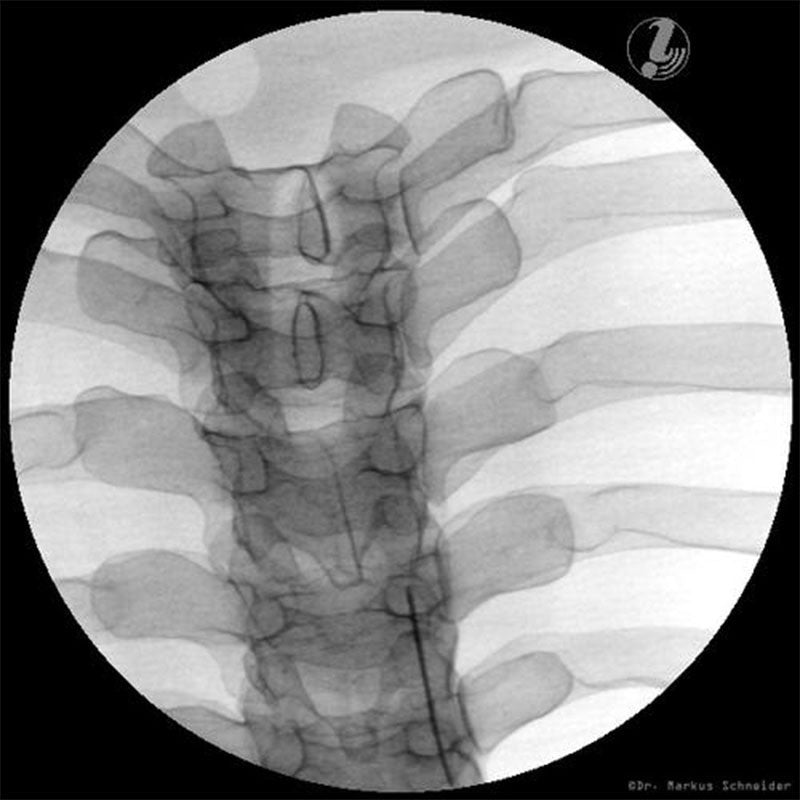

The 3B Scientific Thoracic Spine Injection Trainer allows medical professionals and students to develop a three-dimensional understanding of the practical medical procedures that take place when carrying out successful spine interventions.

Students will be taught how to correlate imaging with the thoracic spinal anatomy, which is relevant to interventional pain procedures. This knowledge will help medical students to recognise the target tissue and vulnerable structures. Using imaging and anatomic inspection, this Thoracic Spine Injection Trainer will enable students to apply best practices, ensuring patient safety whilst carrying out interventional spine procedures.

- Life-like radiopacity for realistic X-Ray images

- Anatomically accurate bone structure

- Interlaminar Epidural Steroid Injection

- Thoracic Transforaminal Injection

- Vertebrae T3-T8

- Ribs 3-8